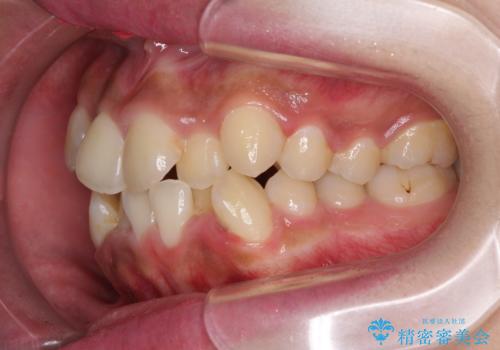

- 八重歯と上下前歯のでこぼこを気にして来院された患者様です。

上下前歯部叢生のスペース獲得のため、上下顎左右小臼歯各1歯(計4本)と全ての親知らずを抜歯して、矯正治療を行うこととしました。

上下の正中位置が大きくずれていたため、治療期間の長期化や正中が合わないまま終了することが予想されましたが、思っていた以上にスムーズに歯が移動し、満足いただける仕上がりとなりました。